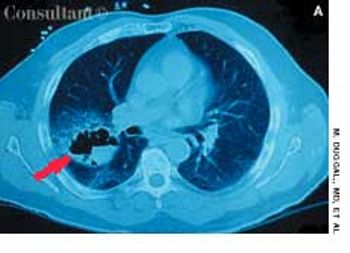

A 2-month history of cough sent a 62-year-old woman for medical evaluation. The patient denied fever, chills, and rigors but reported seeing streaks of blood in her sputum during the past month. The patient had undergone a right nephrectomy 4 years earlier for renal cell carcinoma.